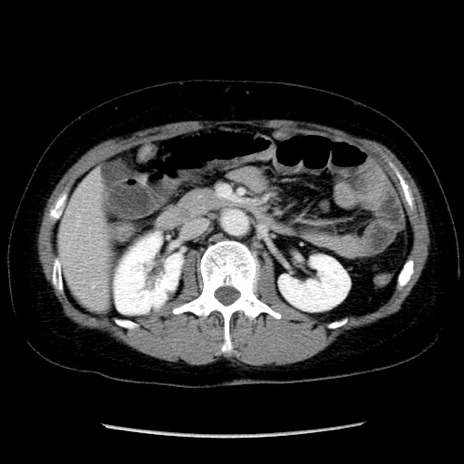

症例6(横断像)

【症例】50歳代女性

【主訴】下腹部痛

【現病歴】本日朝より下痢2回あり。 昼食を食べた後、嘔吐3回、下腹部痛認め、症状軽快せず、当院救急搬送。

【既往歴】卵巣癌術後(8年前に当院で卵巣摘出)

【身体所見】 意識清明、腹部:平坦、腸蠕動音→、やや硬、下腹部自発痛・圧痛あり、反跳痛あり、筋性防御なし。

【データ】WBC 16000、CRP 0.01